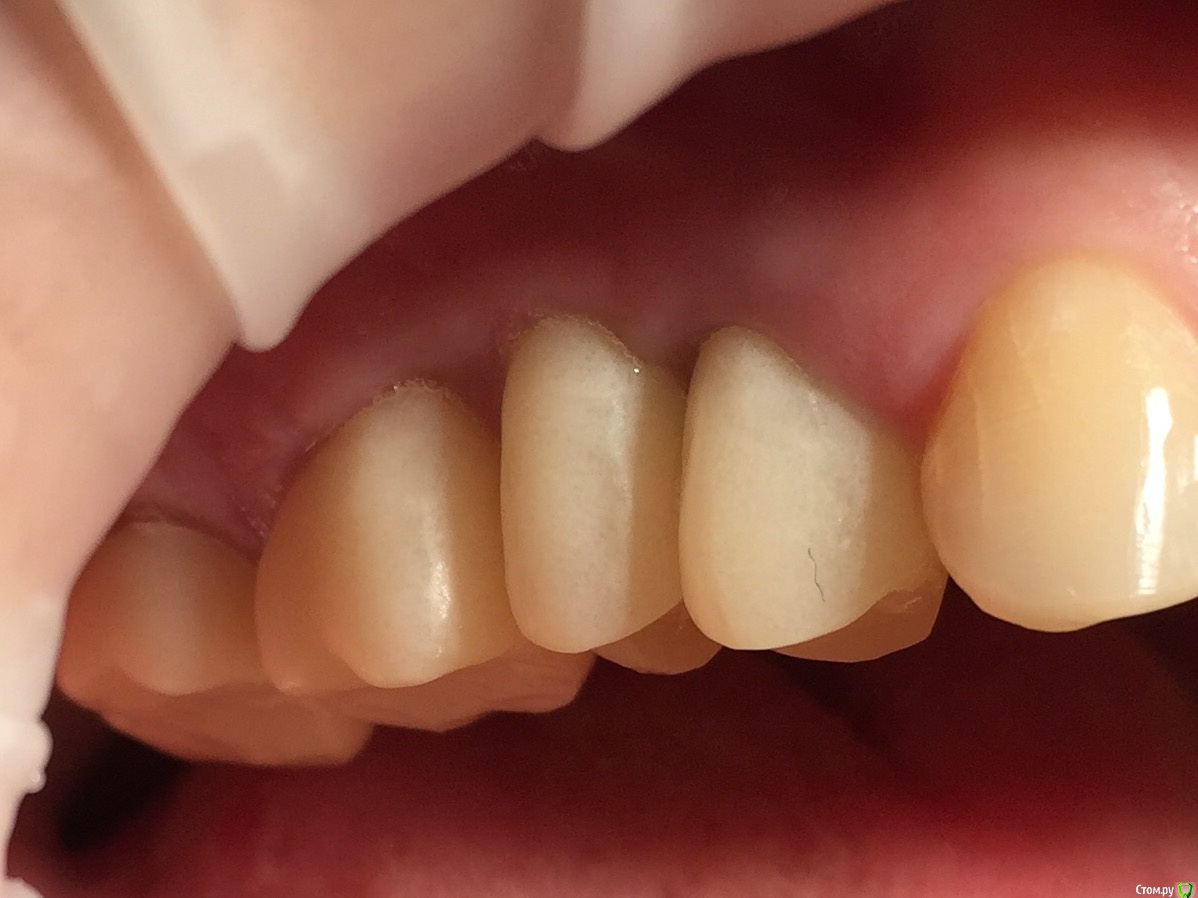

Глеб Митрофанов Опубликовано 12 сентября, 2015 Поделиться Опубликовано 12 сентября, 2015 (изменено) Направлена ортопедом , к которому пришла от другого хирурга и ортопеда , которые оперировали и изготавливали времянки соответственно . Пришла с просьбой - хочу сосочки ! Изменено 12 сентября, 2015 пользователем Глеб Митрофанов Ссылка на комментарий

Глеб Митрофанов Опубликовано 12 сентября, 2015 Автор Поделиться Опубликовано 12 сентября, 2015 А какой вопрос? С какой целью написали?Что возможно сделать , чтоб сделать максимально приближенное к желаемому ? Работа с мягкими тканями , времянками ?? Ссылка на комментарий

faity Опубликовано 12 сентября, 2015 Поделиться Опубликовано 12 сентября, 2015 пластика с бугров наверху, снизу полностью переделывать ортопедию и делать пластику с бугров. Гамборена вчера показывал как))) carlos показывает уже год 4 Ссылка на комментарий

Mane Опубликовано 12 сентября, 2015 Поделиться Опубликовано 12 сентября, 2015 снимаешь временную коронкупересаживаешь сст с бугра на тонкий формировательждешь месяцоцениваешьпротезируешь 2 Ссылка на комментарий